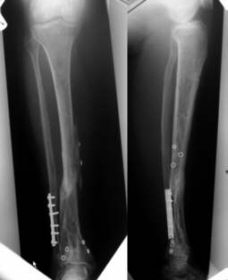

Final outcome after 56 weeks.